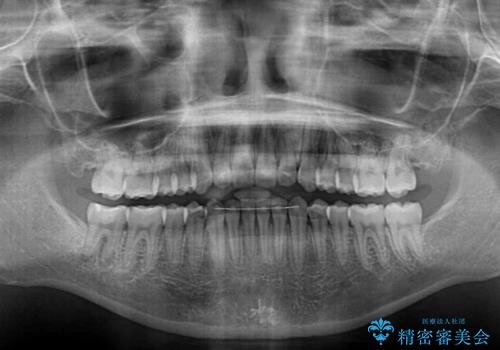

上下前歯が接触しない オープンバイトをインビザラインで改善

- 前歯の上下スペースによる食べにくさを気にして来院された患者様です。

インビザラインにより上下の前歯の隙間を閉じていくこととしました。

上下の奥歯を圧下させるようにすることで、前歯を接触させるように計画しました。

上下の隙間に舌が入り込むことがオープンバイトの原因であったため、舌の筋肉のトレーニングも並行して行い、後戻りの抑制を図りました。